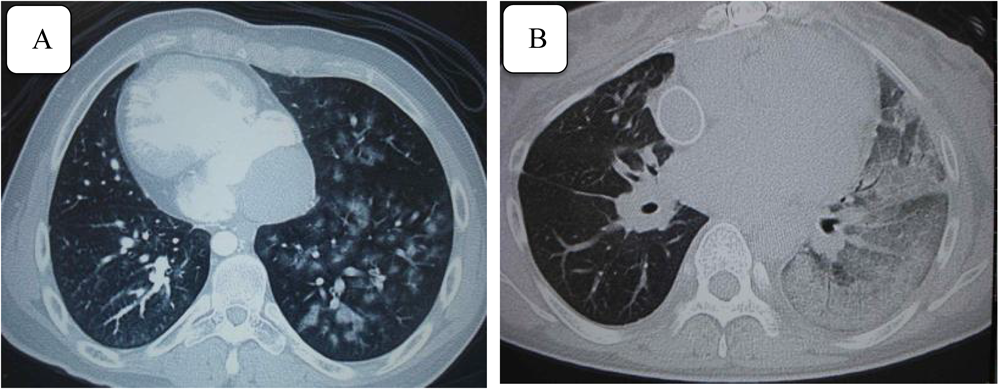

Fig. 3 Thoracic computed tomography (CT) findings

A: 19-year-old man. Enhanced CT image shows diffuse alveolar hemorrhage. B: 38-year-old woman. Plain CT image shows left pulmonary hemorrhage.

19歳男性(MA,房室弁人工弁置換術後)はF手術16年後に,び慢性の肺胞出血(Fig. 3-A)を発症,側副血管のコイル塞栓後も喀血を繰り返し,アスピリン中止でも軽快しないため,人工弁にもかかわらずワーファリンの一時減量を余儀なくされた.呼吸器内科を受診し,気管の炎症を抑える目的でクラリスロマイシン少量持続内服を開始したところ,喀血発作が軽減していた.前述の脳梗塞既往のある38歳女性(TAIb)はワーファリンのみ内服中であったが,脳梗塞の3年後の定期検診で左肺の浸潤影を指摘され,当初肺炎を疑われたが徐々に拡大しCTにて肺出血と診断された(Fig. 3-B).診断時のPT-INR 2.29であったためワーファリンの一時的な減量を行い,脳梗塞再発することなく軽快した.